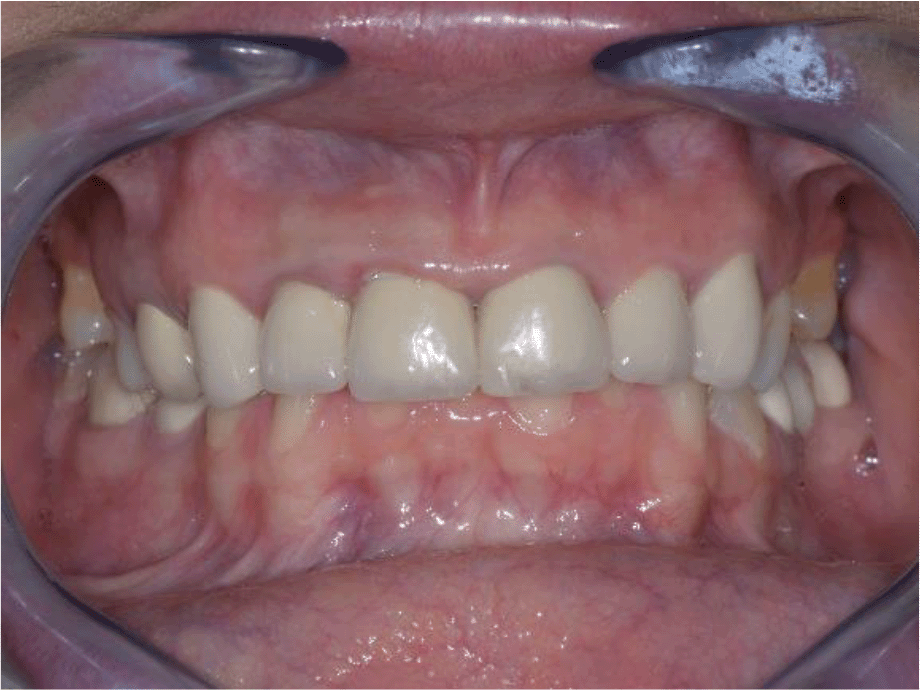

The patient reported a lack of symptoms of TMJ after 3 months, establishing the therapeutic effect of the splint. We then proceeded to the final prosthesis. All constructions were made of ceramics based on zirconium dioxide, with added yttrium and hafnium oxides. The distal defects of the lower jaw were solved with bridge constructions, and single crowns were placed on the frontal teeth (Figures 19 and 20).

All of the final constructions were made from Ceramill Zolid FX MultiLayer B2 and Glase (AmannGirrbach). For the upper jaw, single zirconia crowns of the canines and block crowns of 11, 12 and 21, 22, respectively, were made, for the distal defects - bridge restorations of zirconia ceramics. The distal structures of both jaws were cemented first to ensure stable occlusion. Then the crowns were fixed almost at the same time in the frontal section (Figures 21 and 22).